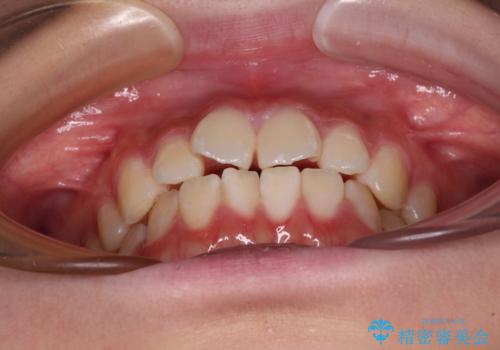

- 上下前歯のねじれを気にして来院された患者様です。

ワイヤー矯正でもマウスピース矯正でも対応可能でしたが、マウスピース矯正の自己管理が面倒であること、上顎前歯の捻転が著しいことから、ワイヤー矯正での治療を希望されました。